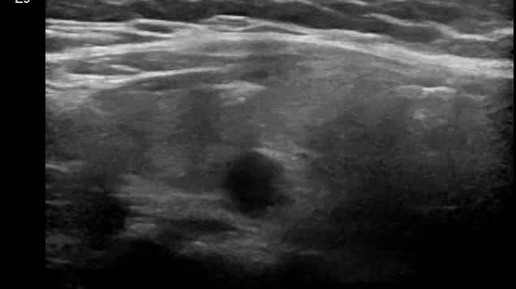

Видео к статье "Стратификация узлов щитовидной железы. TI-RADS-5" https://dzen.ru/a/ZwTJQTbM3zpM5Y6F

Ультразвуковые находки от врача УЗД Зорина Я.П.